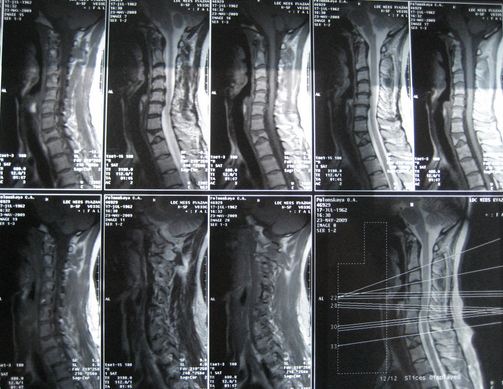

Как происходит лечение?